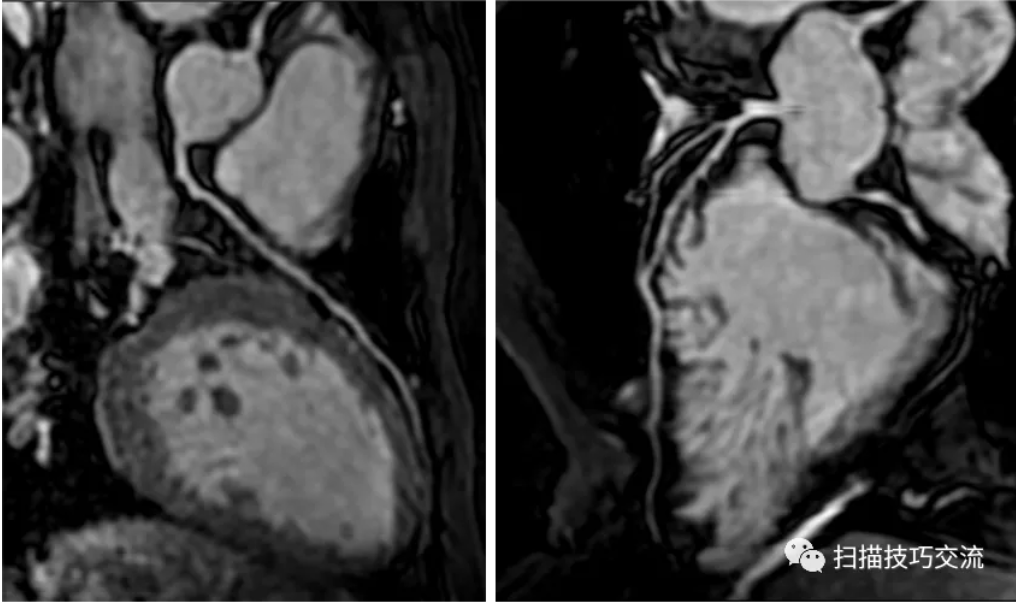

3,成像效果

图像来自上海平安融胜医学影像诊断中心,非常感谢钱莹教授提供图像。